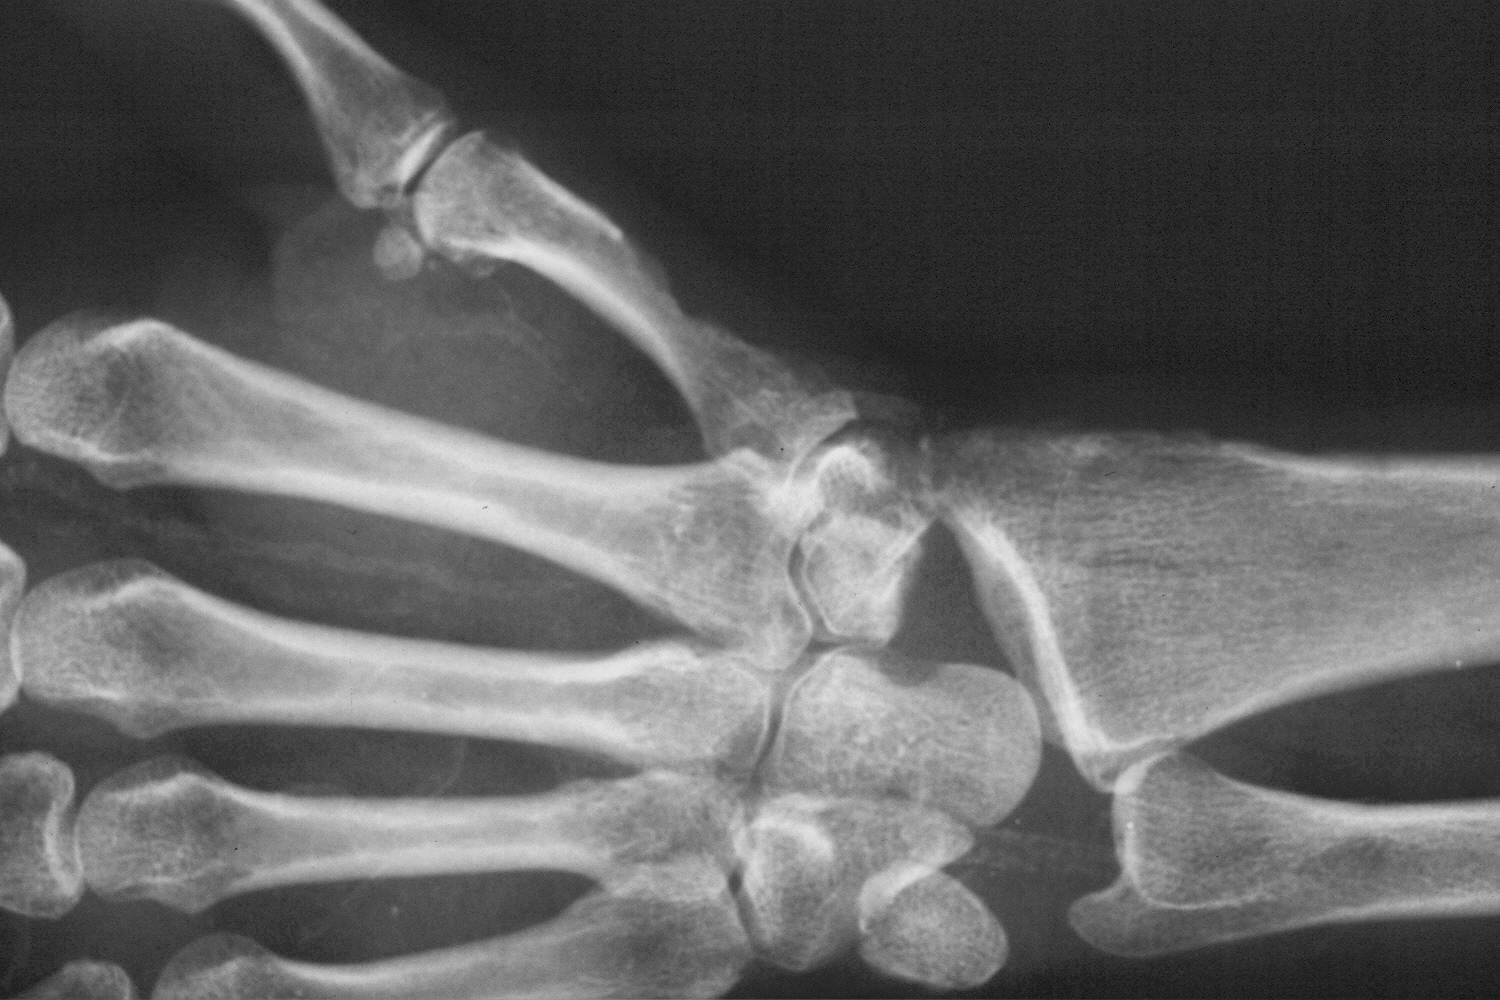

Final result.

Preop.

Postop.